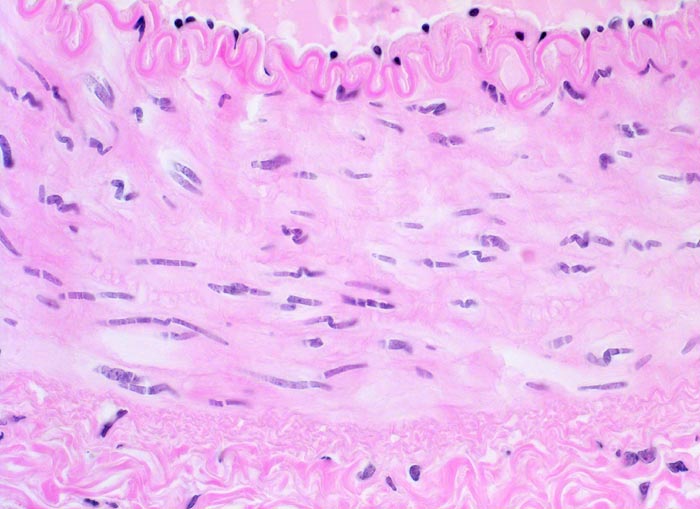

Arterie

Normalbefund

Blutgefäss

Kardiovaskuläres System

Die Endothelzellen mit wenig subendothelialem Bindegewebe sitzen auf einer prominenten gewellten Lamina elastica interna. Die dünnere Lamina elastica externa ist in dieser Färbung nicht abgrenzbar. Die Kerne der glatten Muskelzellen der Media sind langgestreckt und verlaufen gewellt.

Histologie

400